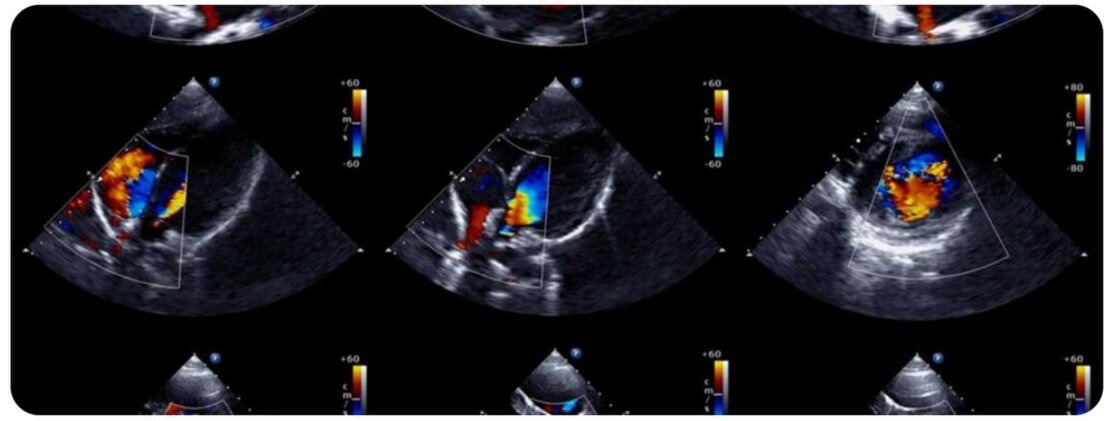

Ecocolordoppler

L’Ecocolordoppler vascolare è una metodica diagnostica non invasiva, che permette la visualizzazione ecografica dei principali vasi sanguigni e lo studio del flusso ematico al loro interno.

L’esame viene effettuato appoggiando una sonda sulla pelle del paziente. La sonda in questione emette ultrasuoni, onde sonore ad alta frequenza non percepibili dall’orecchio umano, che subiscono deviazioni dalle varie strutture del corpo umano, che poi a loro volta vengono analizzate dalle apposite sonde ecografiche ed inviate all’unità centrale. Un computer elabora le onde riflesse e permette agli esaminatori di valutare sul monitor un’immagine rappresentativa e diversa per ogni tipo di tessuto. Grazie a questa ricostruzione gli esaminatori sono in grado (una volta acquisite le nozioni base) di poter capire quando ci si trovi di fronte a strutture considerate “normali” o quando ci si trovi di fronte ad alterazioni “anormali” o meglio patologiche.